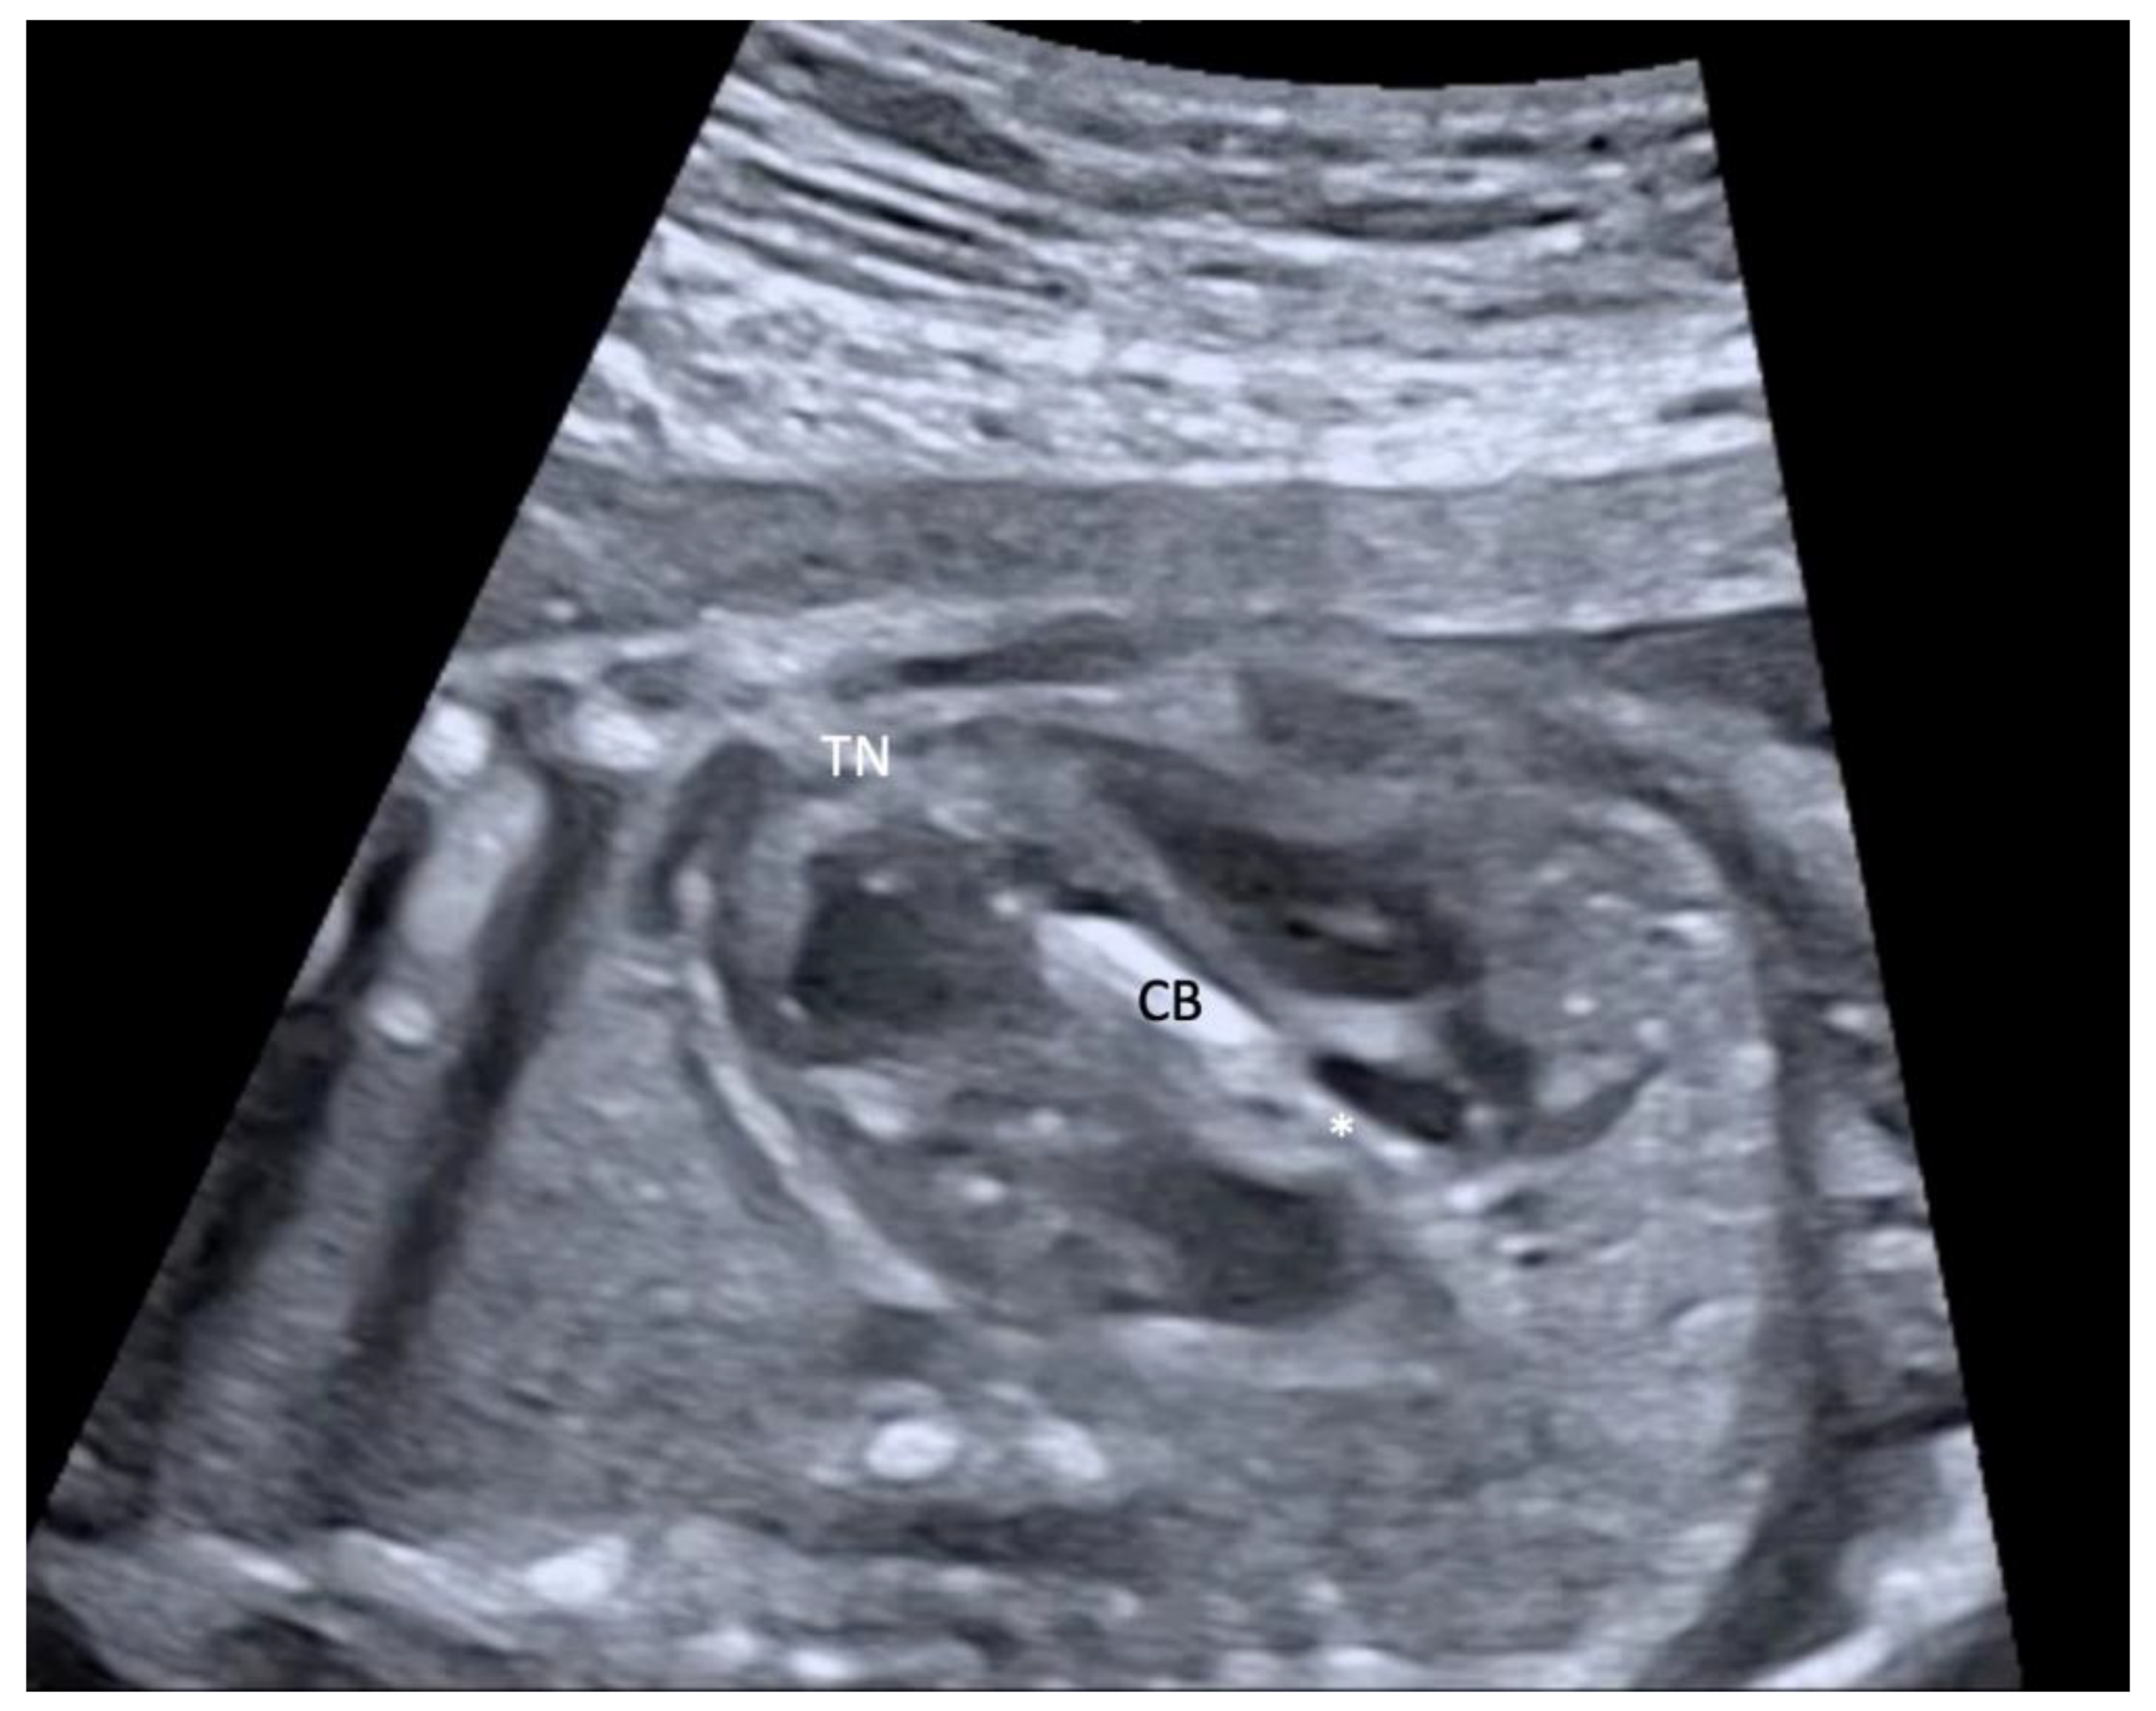

2.2. Procedure